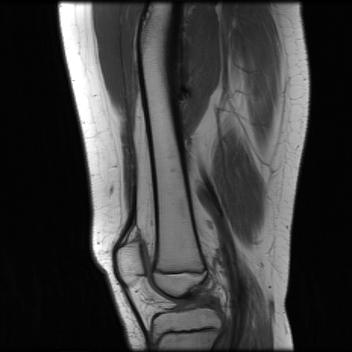

Test data: For evaluation, we used the ten 352352 MRI images in Fig. 2, which were not in the training dataset. The measurements were constructed using (1) with complex AWGN whose variance was adjusted to give a pre-masking SNR of 40 dB. For the multicoil experiments, we used coil sensitivities simulated using the Biot-Savart law, while in the single-coil case, we used .